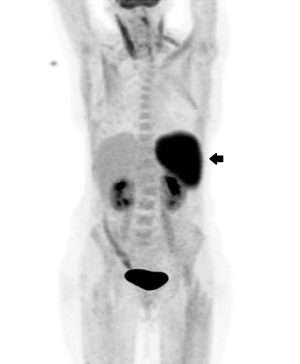

A CT image of her chest showed unchanged pulmonary nodularity, and splenomegaly that was new since her previous CT chest scan. As there was still no diagnosis after 4 weeks of investigations, fine needle aspiration of a lung nodule was attempted, without success. Due to ongoing concerns about possible malignancy (pulmonary or haematological), a positron emission tomography scan was performed. The lung nodules were not fluorodeoxyglucose (FDG)-avid; however, the spleen was found to be intensely hypermetabolic, as shown by increased FDG uptake (Box 1).